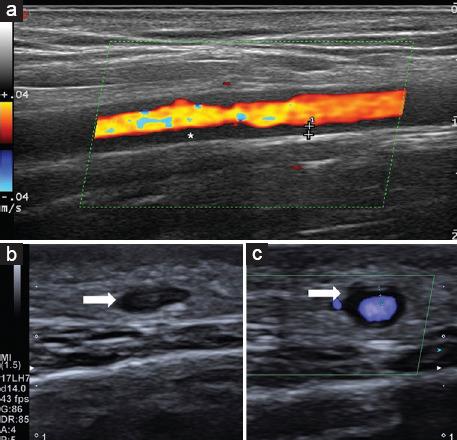

Abstract Image